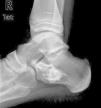

Se presenta el caso de un varón de 9 años que acude a urgencias por dolor en pie derecho de aparición aguda. Radiológicamente existe una lesión osteolítica en calcáneo, que ocupa la mitad del cuerpo, con características de benignidad (fig. 1). El TC muestra una imagen compatible con QOS. Debido al tamaño de la lesión y al riesgo de colapso, se indica el tratamiento quirúrgico: se realiza una ventana en la cortical externa del calcáneo, se curetean las paredes de la cavidad, se perforan las paredes del quiste, y se rellena la cavidad con injerto óseo heterólogo liofilizado (Prosteon®). La anatomía patológica confirma el diagnóstico de QOS. El paciente inicia carga parcial a las 4 semanas de la operación y a los 3 meses inicia actividad deportiva sin dolor. A los 2 años de evolución, radiológicamente se observa la desaparición de la pared esclerosa del quiste, con reabsorción parcial del injerto aportado que es sustituido por hueso trabecular (fig. 2) dando por curada la lesión.